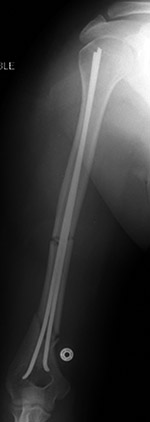

Flexible fixation rods |

Flexible intramedullary fixation rods stabilize a healing humerus shaft fracture. The wire in the eyelets distally (arrow) prevent the rods from backing out of the insertion portal. From Hunter, 1994 |